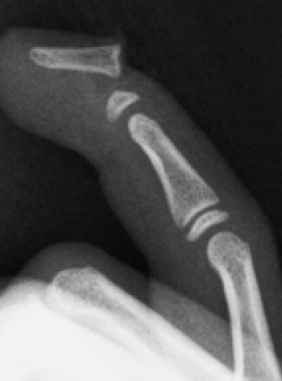

D3. Fracturas del cuello (subcondíleas)

Es una fractura extraarticular frecuente en la edad infantil y característica de lesiones por aplastamientos al cerrarse puertas de manera brusca al retirar la mano. Es más frecuente en la falange media del 2º o 5º dedo. El fragmento distal tiende a rotar a la extensión permaneciendo los ligamentos colaterales insertados en el fragmento distal.

Las fracturas no desplazadas del cuello de la falange se manejan con inmovilización con flexión de la articulación interfalángica durante 3-4 semanas. A pesar de ser fracturas alejadas de la fisis, en niños con potencial de crecimiento, menores de 8 años, se produce una buena remodelación de la fractura sin dejar secuelas cuando el desplazamiento es leve (Figura 23).

En el caso de fracturas muy desplazadas e inestables deben reducirse de manera cerrada y estabilizar con agujas cruzadas que se mantienen durante 3-4 semanas.

Se debe evitar atravesar la superficie articular con las agujas y utilizar agujas de diámetro adecuado para evitar secuelas, aunque en ocasiones es imposible sintetizarlas sin atravesar la articulación (Figura 24).

Figura 24: a- Fractura del cuello de falange media con desplazamiento posterior que requiere tratamiento quirúrgico. b- Reducción cerrada y estabilización con agujas de Kirschner.